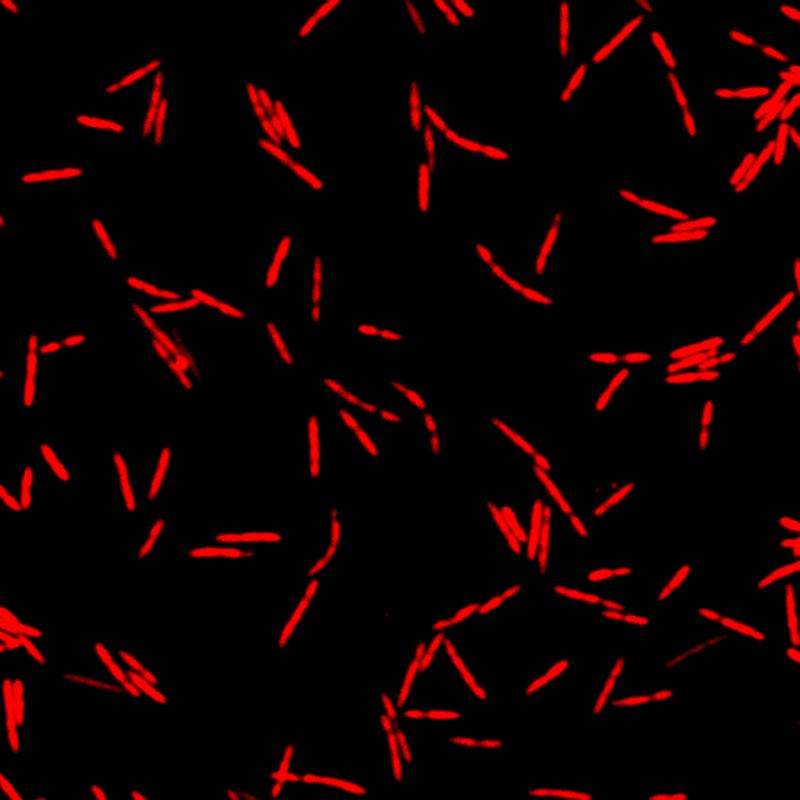

Genau hier setzen die Würzburger Wissenschaftler:innen an. „Wir haben ein dringend benötigtes Instrumentarium für den Einsatz in Fusobacterium nucleatum entwickelt und erstmals auch ein Fluoreszenz-Bildgebungsverfahren etabliert, mit dem wir die Mikroorganismen darstellen und verfolgen können“, erläutert Falk Ponath, Erstautor der kürzlich in dem Fachmagazin PNAS (The Proceedings of the National Academy of Sciences) erschienenen Studie. Mithilfe ihrer genetischen Werkzeuge hat das Team einen Faktor entdeckt, der womöglich zur Kontrolle der Adhäsion der Onkomikroben an Tumorzellen beiträgt.